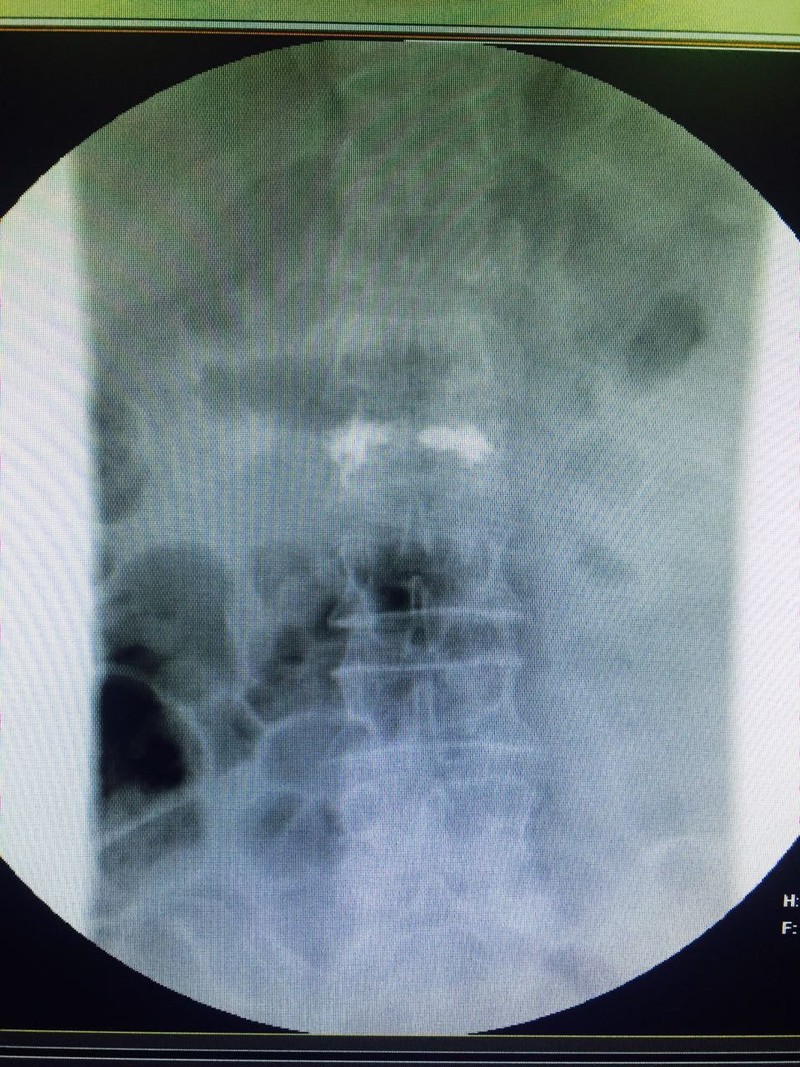

الحقن الإسمنتي للفقرات احد الحلول لعلاج الكسور المرضيه الناتجه عن هشاشة العظام

حيث حضرت مريضه٧٠ سنه تعاني من كسر انضغاطي لفقره قطنيه وبعد العرض علي د حازم

فريد جراح العمود الفقري تم عمل الفحوصات اللازمه والتي أظهرت وجود هشاشة بالعظام

وعلي الفور تم التدخل الجراحي لعمل حقن إسمنتي للفقره المنضغطه بعد رد الانضغاط وذلك من

خلال جرح صغير جدا لا يتعدي ١ سم وغادرت المريضه في نفس اليوم بعد عدة ساعات من

الجراحه وهي بحاله جيده جدا مع تحسن ملحوظ بالم الفقرات